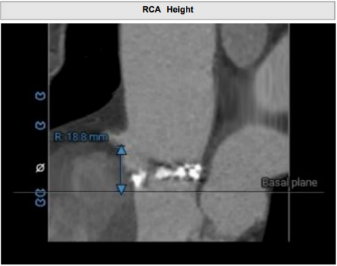

通过术前测量,对病例深入分析,结合人工智能术前分析辅助决策软件进行三维和二维图像融合,郭应强教授指出本例手术存在以下难点:

• 左冠高度8.3mm,左窦瓣叶长度10.2mm,瓣叶明显增厚,应注意术中冠脉闭塞风险。